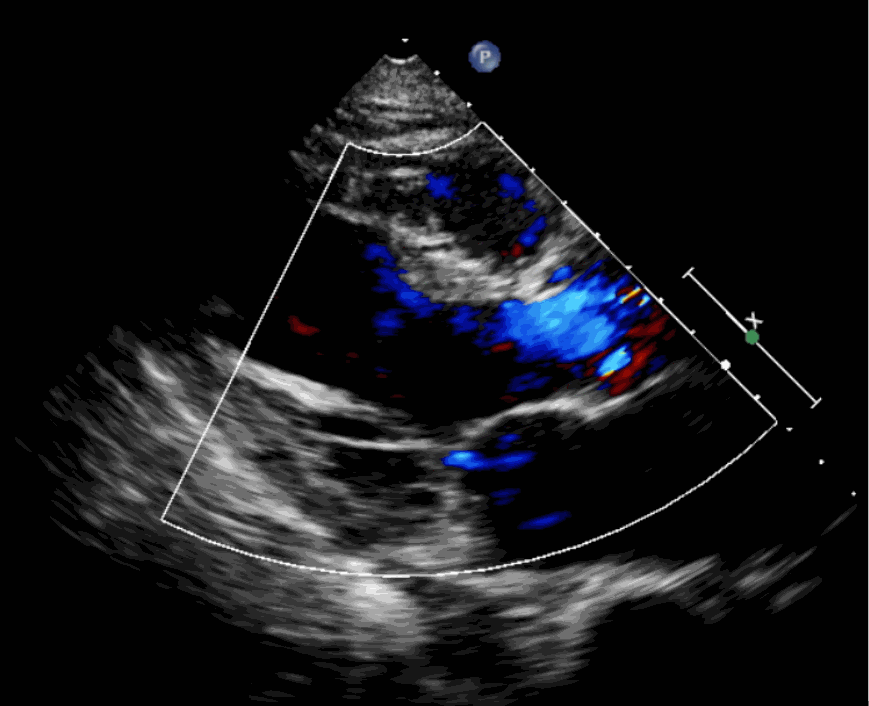

術(shù)后超聲影像圖

手術(shù)采用經(jīng)心尖入路,對(duì)患者進(jìn)行全麻后,在左側(cè)心尖處做3-4cm微創(chuàng)手術(shù)切口,在DSA及超聲引導(dǎo)下手術(shù)順利完成。從導(dǎo)入器械到完成瓣膜置入,僅耗時(shí)約10分鐘。術(shù)后即刻主動(dòng)脈瓣返流程度由術(shù)前大量返流轉(zhuǎn)為消失,患者于導(dǎo)管室拔除氣管插管,次日由ICU轉(zhuǎn)入普通病房。